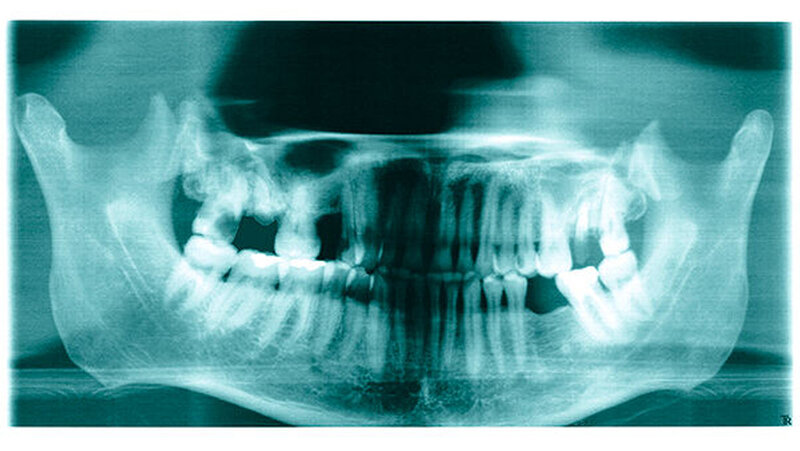

Am 14. März 2003 wurde in der Waal, bei der Gemeine Tiel (Niederlande) ein toter Mann gefunden. Er scheint aus Deutschland zu kommen. Allem Anschein nach lag die Leiche zwischen zwei bis vier Wochen im Wasser.

Das Alter des Toten wird zwischen 30 und 50 Jahren geschätzt. Er hatte schwarze Haare und trug einen Schnurrbart. Seine Größe betrug etwa 175 Zentimeter. Er trug blaue Adidas Sportschuhe in Größe 42, eine blaue Jeans der Marke EDWIN, Größe W31-L32 und dazu einen schwarzen Pullover mit Rollkragen. An seinem rechten kleinen Finger hatte er einen goldenen Trauring. Der Mann war beschnitten.